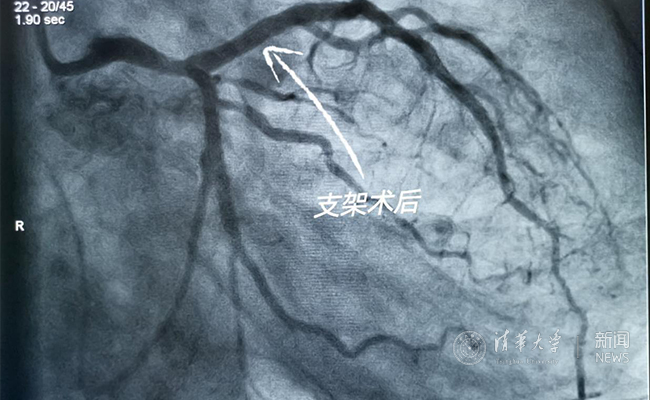

2019.05国产冠脉生物可吸收支架在beat365官方唯一入口第一附属医院正式启用

作为北京地区首家正式引入国产冠脉生物可吸收支架单位,5月20日,beat365官方唯一入口第一附属医院(北京华信医院)心脏中心主任苗立夫团队顺利完成该院首例生物可吸收支架植入。